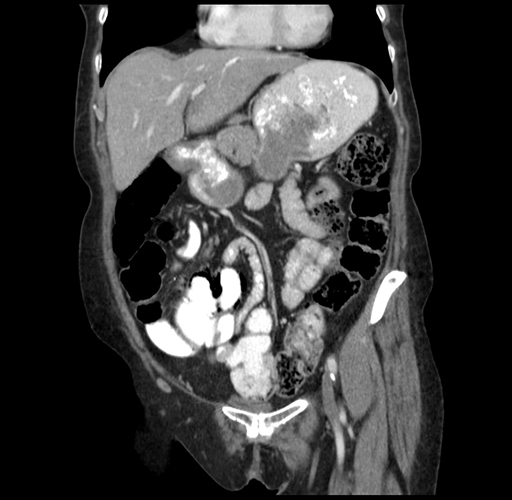

Pre-Chemo: Coronal Venous